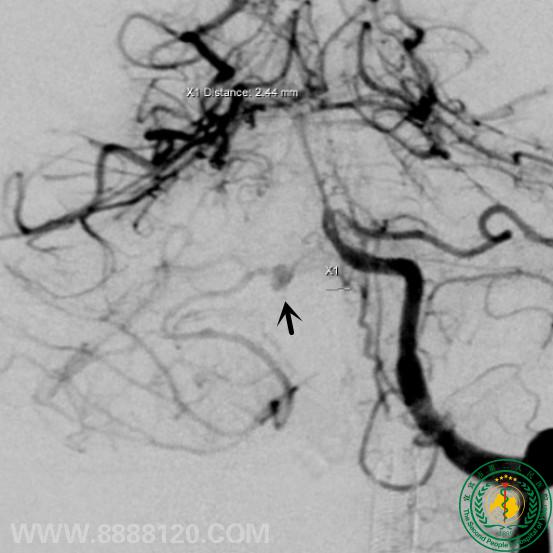

我科完成一例小脑前下动脉 (AICA )动脉瘤介入治疗

我科完成一例小脑前下动脉 (AICA )动脉瘤介入治疗9588